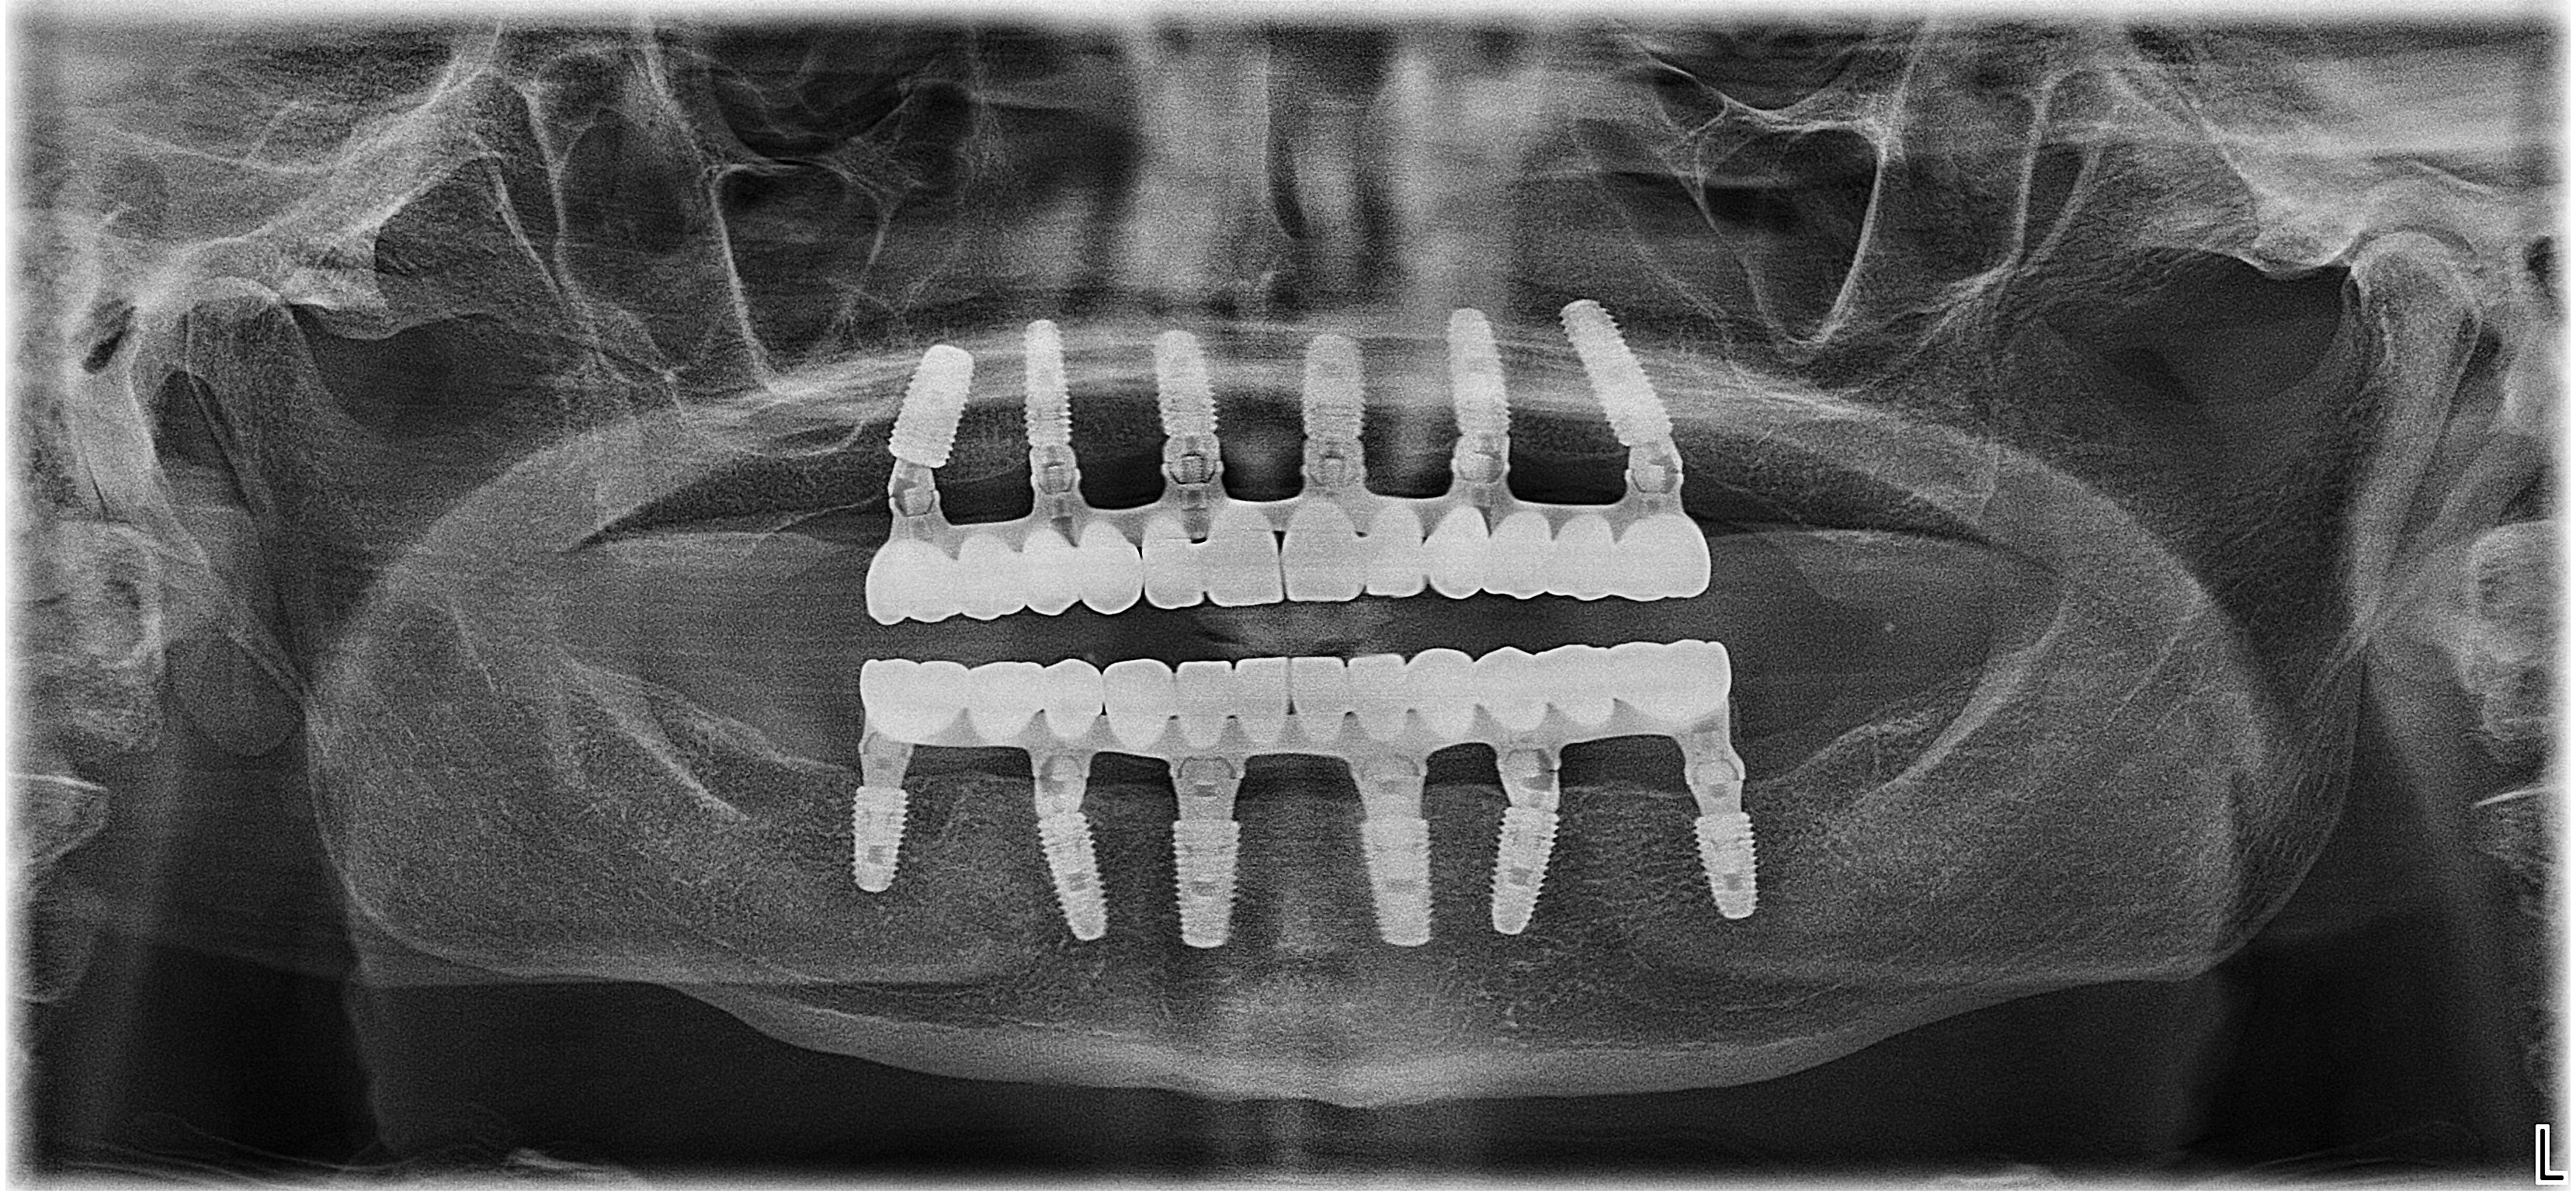

40.351

de implanturi dentare

978

de implanturi zigomatice inserate

5.510

arcade reabilitate pana in prezent

Pacienții noștri se încred în noi datorită profesionalismului demonstrat în timp. Vezi experiența clinicilor DentOP în cifre, actualizate anual:

Sistemul Dantură pe implanturi dentare implică un număr redus, dar totuși extrem de eficient de implanturi dentare, care inserate în poziții cheie conferă siguranța de care ai nevoie / siguranța unei danturi sănătoase. Mai mult decât atât, această intervenție este minim invazivă, iar recuperarea este mult mai ușoară.